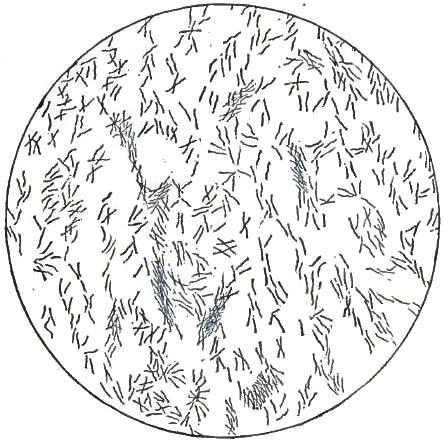

| FIGURE | |

| 4. | BACTERIA FROM GELATIN SOLUTION |

| 7. | BACILLI FROM SWAMP-MUD |

| 8. | BACILLI FROM SEPTICÆMIC RABBIT |

| 9. | BACILLI FROM HUMAN SALIVA |

| 10. | BACILLUS ANTHRACIS |

| 11. | BACILLUS TUBERCULOSIS |